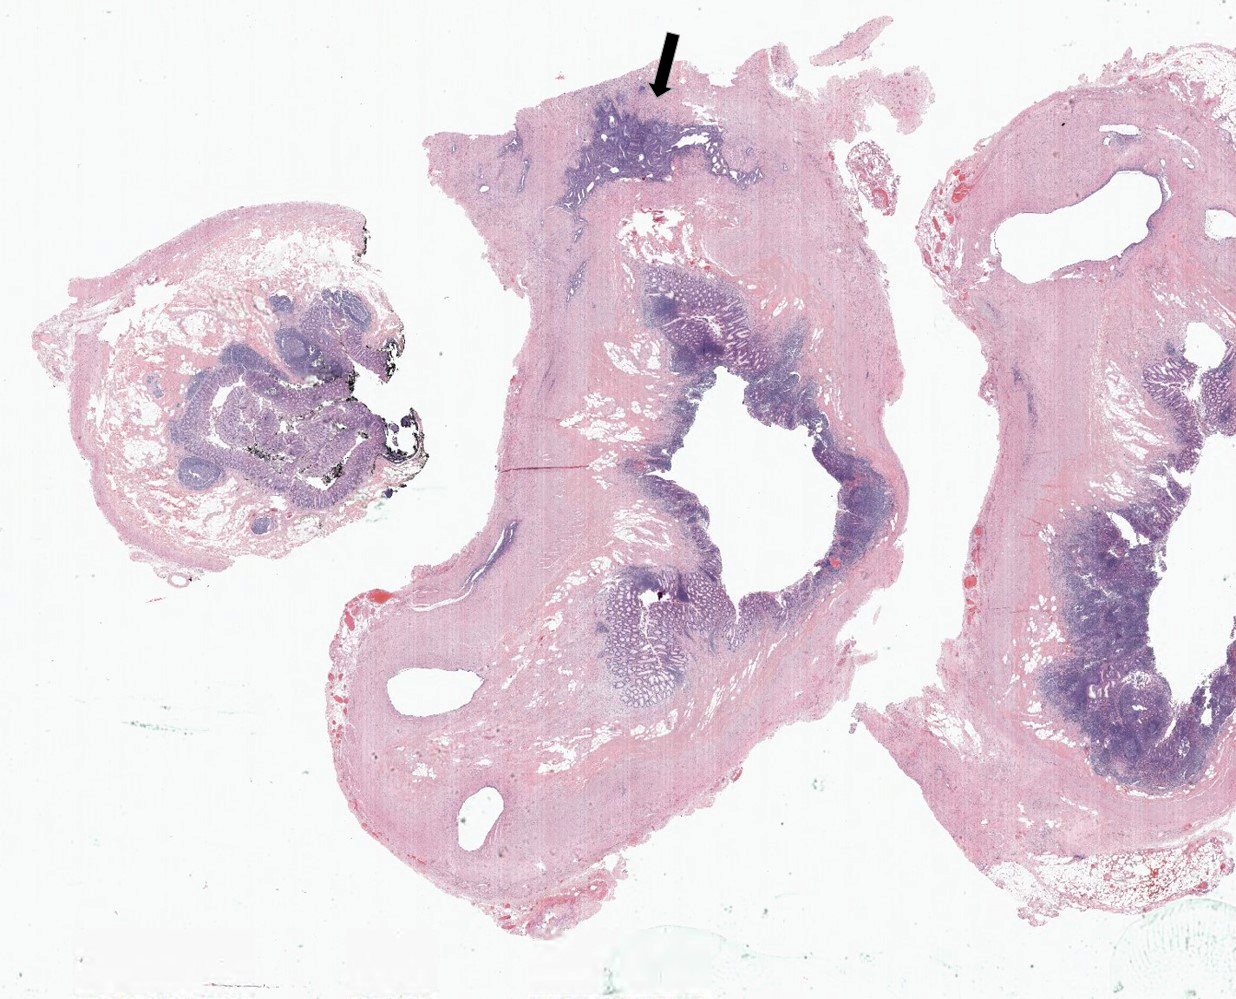

Microscopic (histologic) description

- Variable acute inflammation with predominance of neutrophils; involves some or all layers of the appendiceal wall

- Process may be divided into acute focal, acute suppurative, gangrenous and perforative

- Early lesions display mucosal erosions and scattered crypt abscesses

- Later, the inflammation extends into the lamina propria and collections of neutrophils are also seen in the lumen

- Mural necrosis in gangrenous appendicitis

- Process may be divided into acute focal, acute suppurative, gangrenous and perforative

Microscopic (histologic) images

- Appendiceal diverticulosis:

- Congenital (true) or acquired (false) (incidence 0.014% and 1.9%, respectively) (Hum Pathol 2008;39:1823)

- Occurs in relatively older age group (Surg Today 2012;42:363)

- Symptoms mimic acute appendicitis; higher risk of perforation than acute appendicitis (Surg Today 2012;42:363)

- Often associated with higher risk of neoplasm, especially neuroendocrine tumor and mucinous neoplasms (Int J Surg Case Rep 2017;33:31)

A 40 year old caucasian man presented into the emergency room with right lower quadrant pain associated with vomiting, abdominal tenderness, fever and moderate leukocytosis. Acute appendicitis was suspected and he underwent an appendectomy. His appendix was sent to pathology for histological evaluation. The H&E images are shown above. Which of the following is the most likely diagnosis?

- Appendiceal diverticulitis

- Appendiceal endometriosis

- Interval appendicitis

- Low grade appendiceal mucinous neoplasm